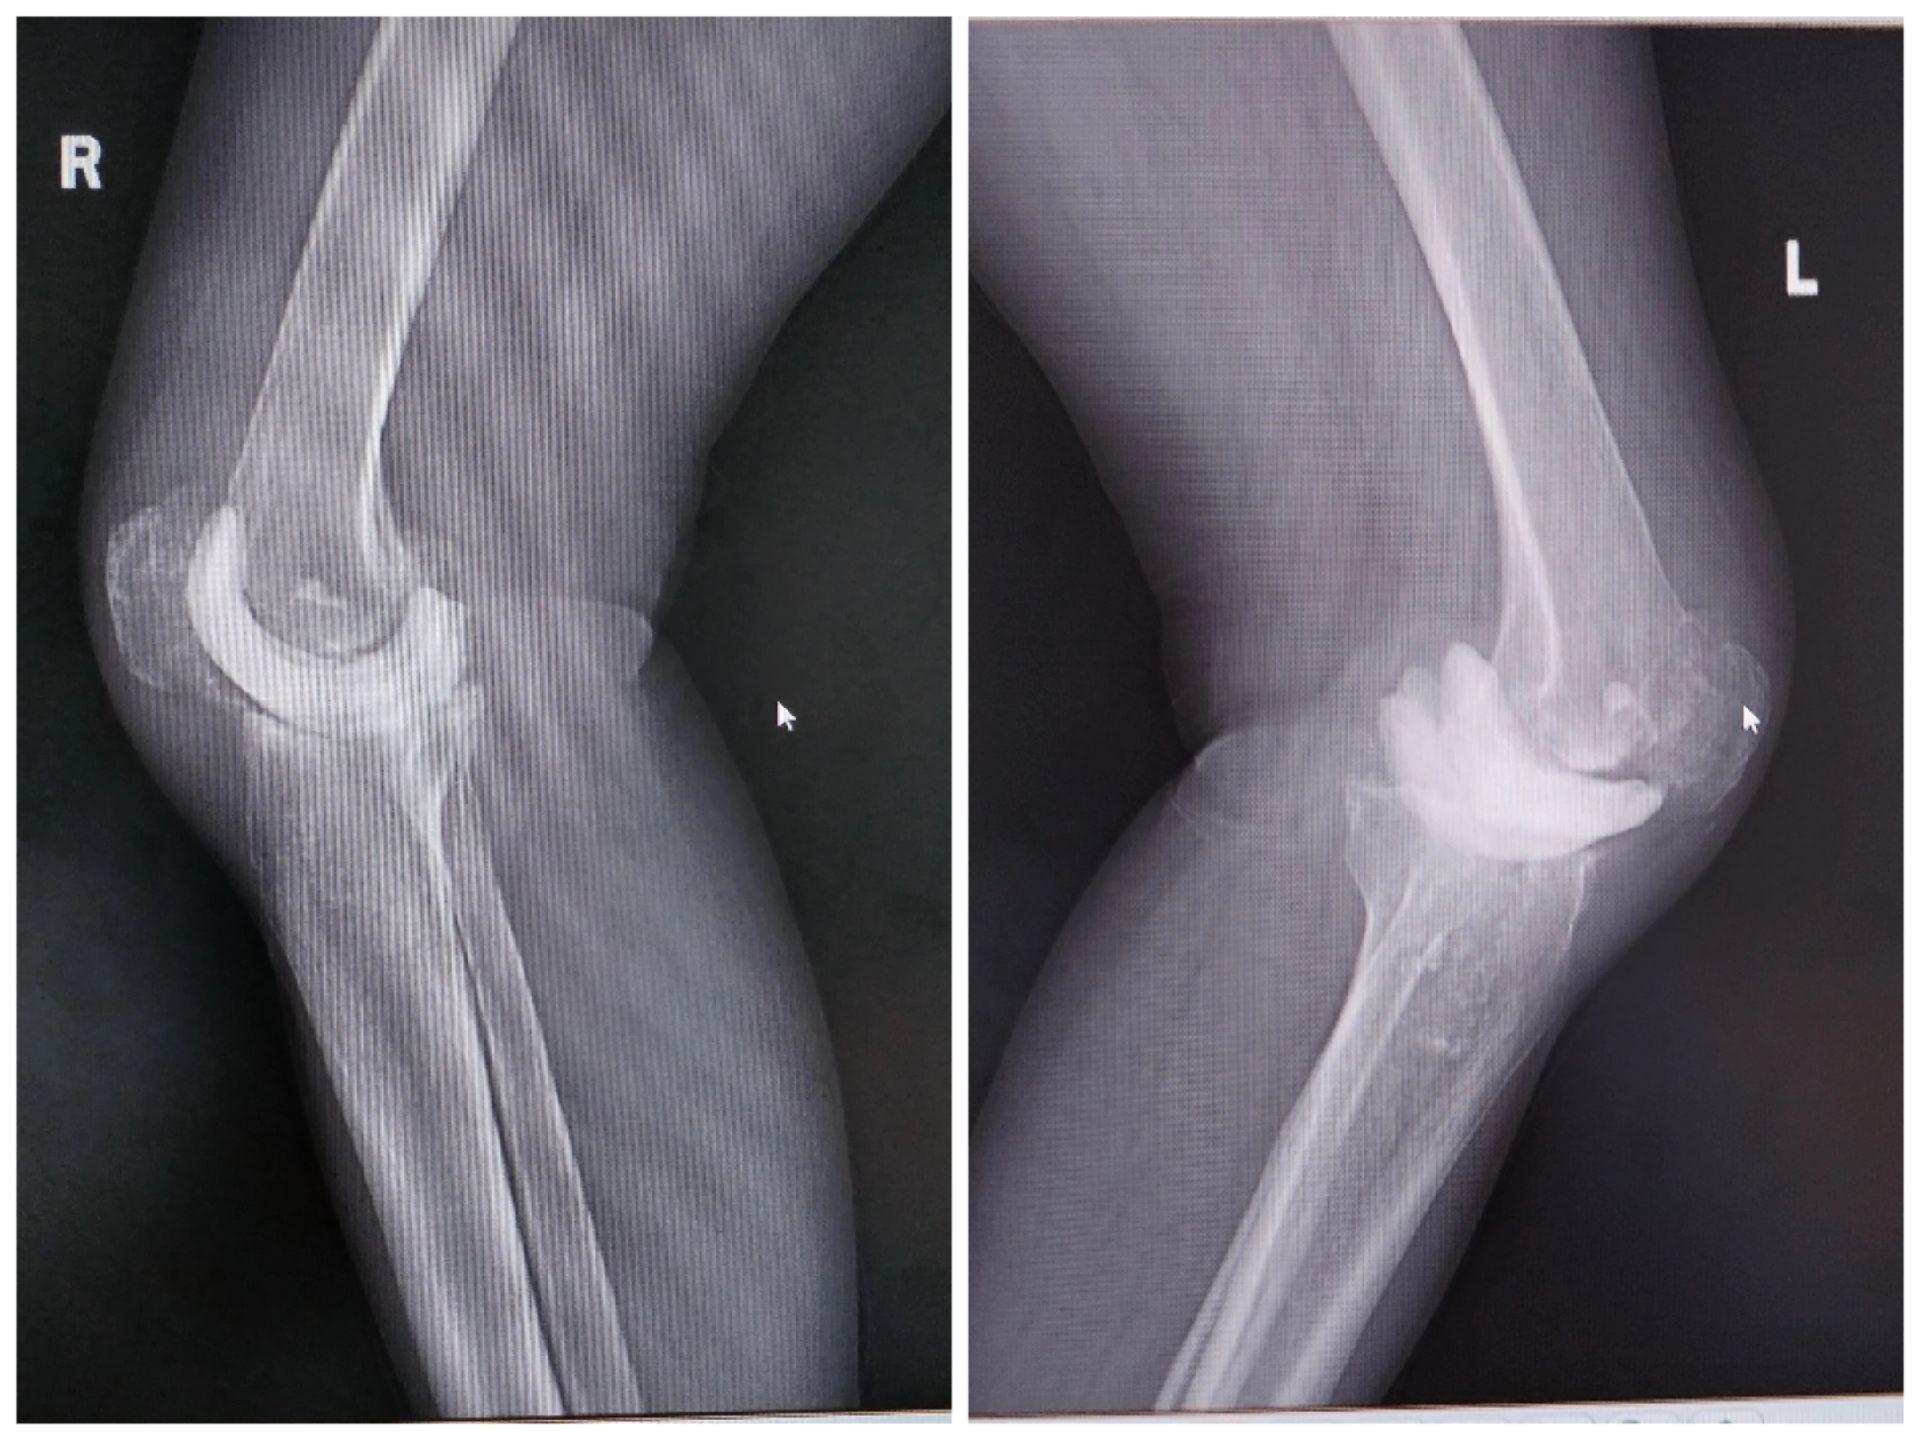

膝关节翻修术。双膝关节置换术后布氏杆菌感染(外院),清创旷置后二期翻修,重新走出自信的步伐。膝关节翻修

膝关节翻修术。双膝关节置换术后布氏杆菌感染(外院),清创旷置后二期翻修,重新走出自信的步伐。